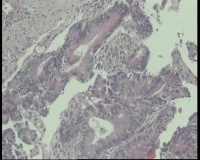

急!请老师帮忙看看,单位同事肠镜病理

进镜达横结肠近肝曲,见不规则增生性肿物,环周生长,表面充血糜烂,触之易出血,肠腔狭窄,镜身无法通过

肠镜活检4块

镜下腺体异型小,纤维间质反应,能直接报结肠腺癌吗?

可一类报告报:管状绒毛状腺癌

高-中分化腺癌。